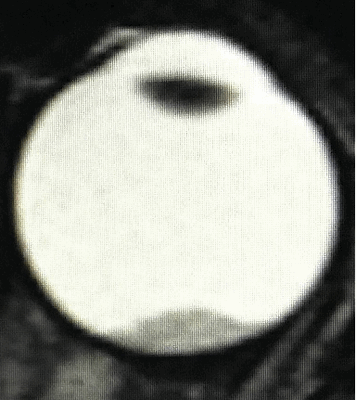

- сниженная острота зрения;

- лейкокория (вы можете увидеть на рис. 1 этот симптом, называемый также «кошачий глаз»), то есть свечение зрачка бело-желтым цветом, когда от поверхности опухоли отражается свет, это нередко заметно на фотографиях;

Рис. 1. Симптом «кошачьего глаза»